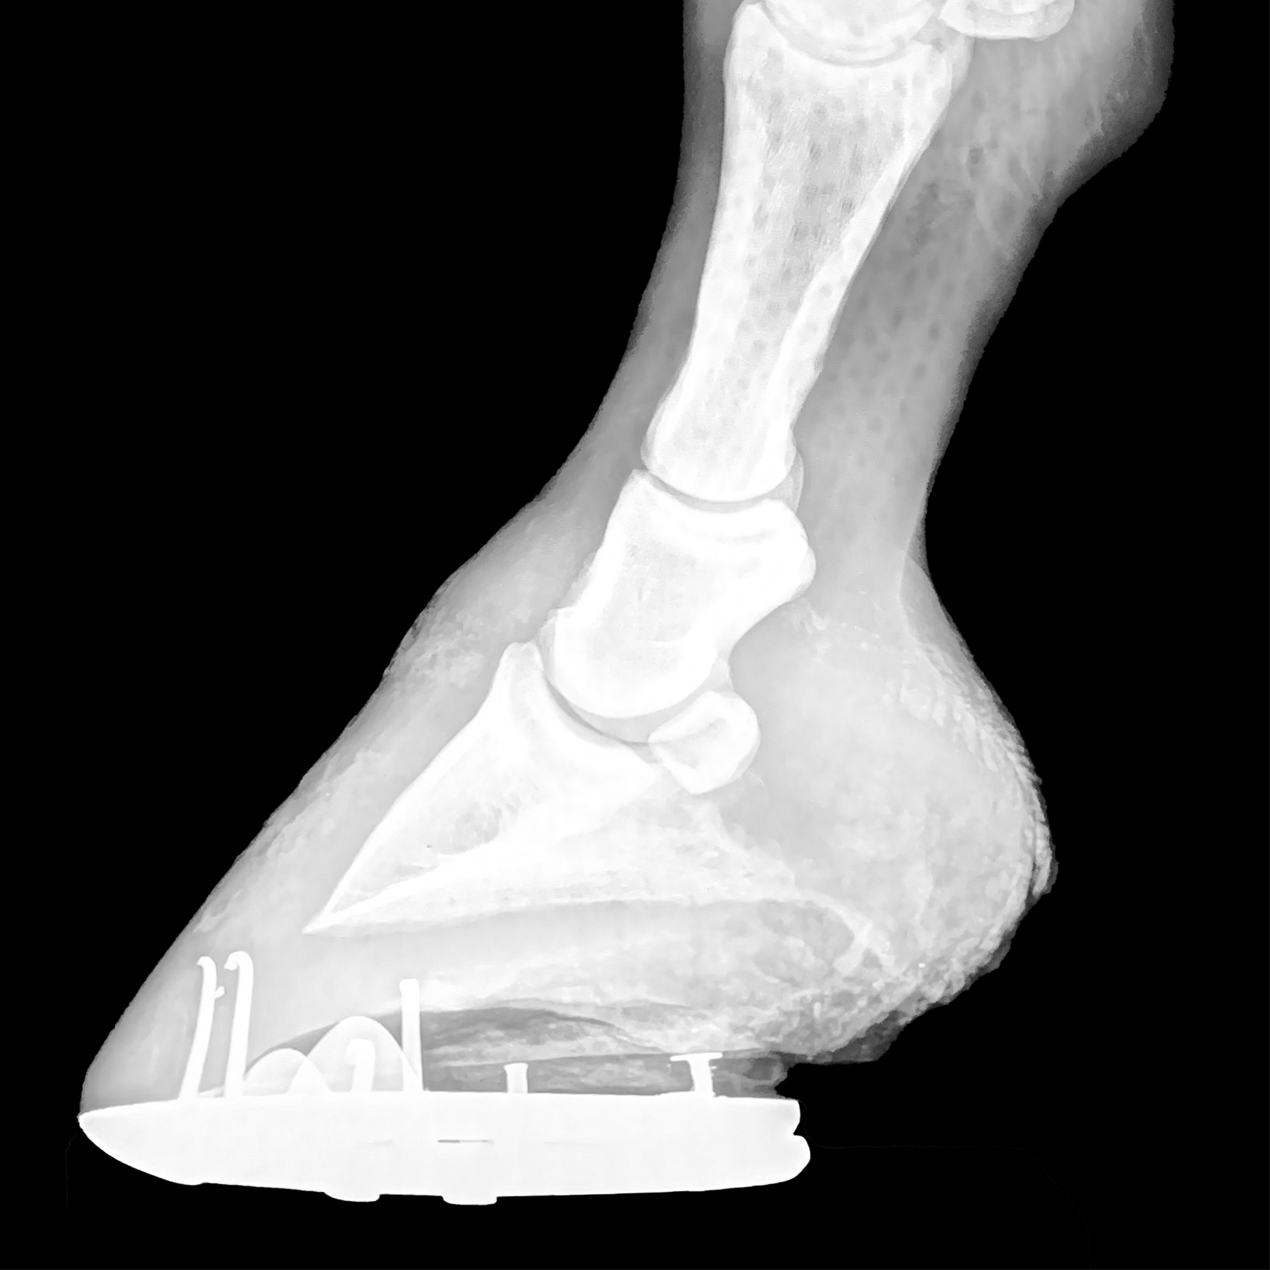

Excessive Distance Between the Coffin Bone and Ground Surface

It can be seen from these two mouseover images above that the hoof presented for shoeing has a very quick breakover. Pay attention to the distance from the point of the frog to the toe of the shoe. The horses stride is substantially shorter with this style of shoeing. The before picture shows that the shoe was set back significantly with a broad toe box to increase the speed and direction of breakover causing the hoof to travel vertically quickly as soon as the hoof leaves the ground. In the final view (mouseover image to see final shoe application) a more normal breakover to correct the hoof flight. The hoof flight will be changed significantly to be a lower and longer trajectory. Of course, this changed increases the length and quality of the stride. Try to investigate the reasoning for the excessive setback of the shoe. Is it solely to keep the shoe from being pulled? Is there a lamness that is the concern? Answer these questions before changing to a more perimeter fit. Making the change will definitely give the horse an easy, appealing gait for pleasure or show.

CALCULATE PAD THICKNESS TO CORRECT HOOF ANGLE

RECOGNIZE THE NEED FOR SUPPORT

DETERMINE THE PROBLEM AND PLAN